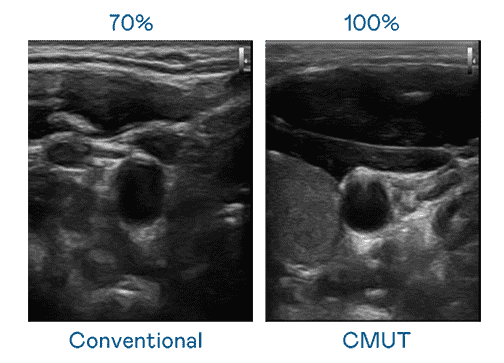

CMUT 技术是一种用电容式微机电元件来产生超音波讯号的技术。。。。与传统 PZT 压电式技术相比,,,,CMUT 频宽增加 30%,,,更宽频的超音波讯号让影像解析度大幅提升,,,是实现高影像品质医疗超音波扫描、、促进精准医疗发展的关键技术。。

大频宽带来超清晰影像

超音波影像的解析度高低,,,首先取决于探头能发出的讯号频宽。。。菠菜论坛 CMUT 可提供高清晰的超音波讯号,,,提供高频宽、、、高灵敏度、、、影像纹理细节更高的超音波影像,,协助医护人员缩短影像判读时间及利用精准的医疗影像进行诊断。。。。